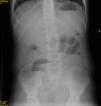

Case 3Female patient aged 5 years with CF DF508, presenting with DIOS of 4 days’ duration with a sudden worsening of symptoms after conservative treatment. A laparotomy was performed, revealing plastic peritonitis and faecal impaction in the distal ileum and colon. Manual disimpaction was performed, followed by caecostomy (Chait procedure) with placement of a Kher tube used in subsequent days to start treatment with antegrade lavage with N-acetylcysteine and PEG. The Kher tube was replaced by a Chait trapdoor (Fig. 1) for continued delivery of enemas, which was removed at seven months. In the four years that followed, the patient had two new episodes of DIOS (Fig. 2) that were treated early with rectal Gastrografin® gravity enemas (in the ward), with resolution of symptoms in both.